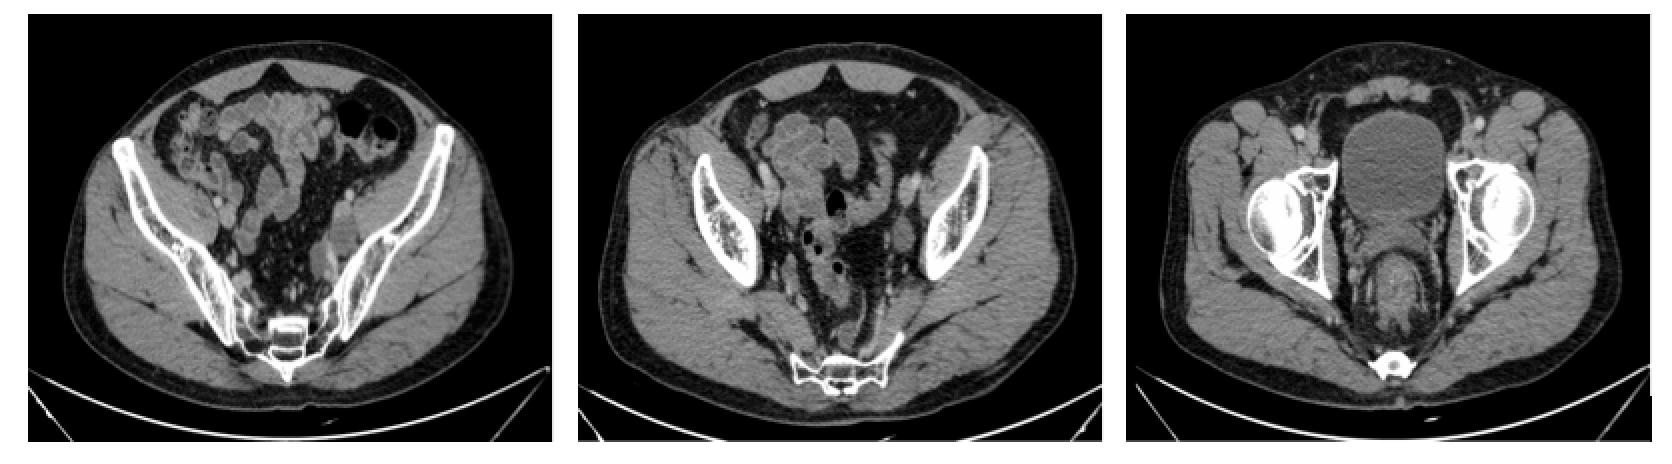

疗效评估(2017.4.26):PR?

全腹CT

直肠中下段肠壁增厚,考虑直肠癌,伴直肠周围间隙、直肠旁间隙、双侧髂血管旁淋巴结增多、增大,与2017-02-14日旧片比较,直肠壁增厚较前减轻,其余未见明显变化,请结合临床及其他检查。

左侧肾上腺结节,转移?腺瘤?或其他?与上述旧片比较未见明显变化。

左肾前下份轮廓欠光整,慢性炎症改变?左肾小囊肿。

肝右后叶上段钙化灶。

前列腺钙化灶。

腹部CT

“直肠癌术后”,未见明显复发征象,请结合临床及其他检查。

腹盆腔少许积液,盆底筋膜增厚。双侧盆壁内侧斑片状及片状不规则低密度影,未见明显强化,积液可能,请随访。

左侧肾上腺结节,转移?腺瘤?或其他?与2017-04-26旧片比较未见明显变化。

左肾前下份轮廓欠光整,慢性炎症改变?

左肾小囊肿。